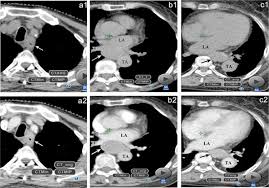

They show the different appearances of acc lung mets. Other names for this test: What is a ct scan with contrast? If not spread, you could conceivably see obstruction or changes in the bowel wall but it would likely be a big tumor nonetheless. I was then directed to lay down on the table.

Abdominal And Pelvic Ct from www.radiologyinfo.org The computer puts them together to make a 3 dimensional (3d) image. Early colorectal cancer can be subtle on ct scans showing only mild wall thickening, small polyps, or subtle lymph nodes in atypical draining location. Nothing found on us scan but fatty liver. I had my half way scan today so i'm now on. This shows the cancer more clearly. Acc has a tendency to spread to the lungs among other organs. Lab tests used to diagnose kidney cancer include: They show the different appearances of acc lung mets.